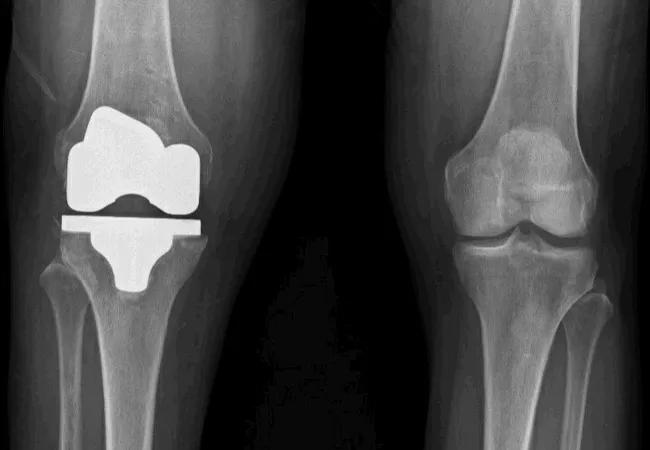

A Look at Subsequent Knee and Hip Replacements: Who Is at Risk and When to Intervene?

A research team, led by an orthopaedic surgeon at Cleveland Clinic, used longitudinal data from the Osteoarthritis Initiative (OAI) to investigate how physicians may better predict if and when a patient is at increased risk of developing contralateral arthroplasty after a total knee or hip replacement. These new insights may be key to developing earlier interventions for at-risk patients.

The investigators identified 332 patients who underwent their first total knee arthroplasty (TKA) and 132 patients who underwent their first total hip arthroplasty (THA) using data that followed the patients for eight years after their initial procedure. Researchers examined the patients at intervals of one, five and eight years.

Results demonstrated that after a TKA, the incidence of contralateral TKA was 14% at one year (95% CI 10 to 18), 33% at five years (95% CI 27 to 39) and 40% at eight years (95% CI 31 to 49). Approximately one in 25 of these patients would later undergo a THA within this eight-year time frame.

After a THA, the incidence of contralateral THA was 9% at one year (95% CI 4 to 13), 18% at five years (95% CI 10 to 26) and 32% at eight years (95% CI 15 to 48). Notably, one in 10 would later receive TKA in the same eight-year period, outpacing their counterparts who required a subsequent THA after the initial TKA. These results were striking, but not surprising to investigators. “One in three patients received a contralateral total knee replacement at the five-year interval. The data suggest that we should be narrowing in on this group,” says Dr. Piuzzi.

The study also finds that medial joint space is a risk factor for developing contralateral TKA. In fact, a 1 mm loss of joint space increased the likelihood of TKA by 42% at 4.1° of varus alignment (HR 1.42 [95% CI 1.29 to 1.56]; p = 0.005), 26% at 1.6° of varus alignment (HR 1.26 [95% CI 1.06 to 1.51]; p = 0.005), and 14% at 0.7° of valgus alignment (HR 1.14 [95% CI 0.89 to 1.46]; p =0.005). “This has a direct clinical implication for physicians as it’s a unique data point that may be used to determine risk for an individual patient,” he says.